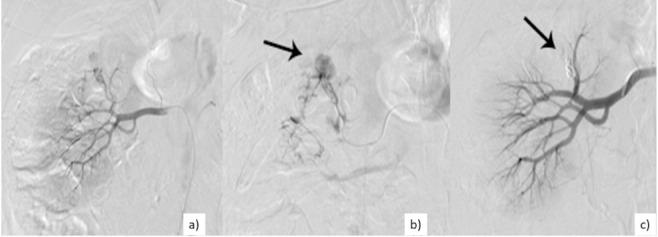

Intraabdominal hemorrhage secondary to liver and kidney injury is a major cause of morbidity and mortality. Endovascular arterial embolization is an established interventional radiology technique used to treat active bleeding, and its role in managing abdominal hemorrhages is growing, given the increasing trend for conservative treatment. Our study aims to retrospectively evaluate the technical and clinical results and the possible complications of arterial embolization procedures performed in emergency, in post-traumatic, iatrogenic, and pathological hepatic and renal bleedings.

We performed a ten-year, single-center retrospective survey (from January 2010 to December 2019) of all patients treated in emergency by intra-arterial embolization of liver and kidney bleeding. Preliminary CT angiography studies were evaluated, as well as the angiographic findings. Materials used, procedural data, and clinical outcomes, including complications, were recorded.

The diagnostic angiography showed a single source of bleeding in 20 cases (66.7%), two bleeding vessels in 4 cases (13.3%), and multiple hemorrhagic sources in 6 cases (20%). All bleeding sources were successfully embolized; in 12 patients (40%), complete embolization was achieved with coils and 18 patients (60%) with hemostatic sponges. In one case, a second embolization procedure was performed for the persistence of hemodynamic instability. No major post-procedural complications were recorded. The mean procedure duration was 65.1 minutes.